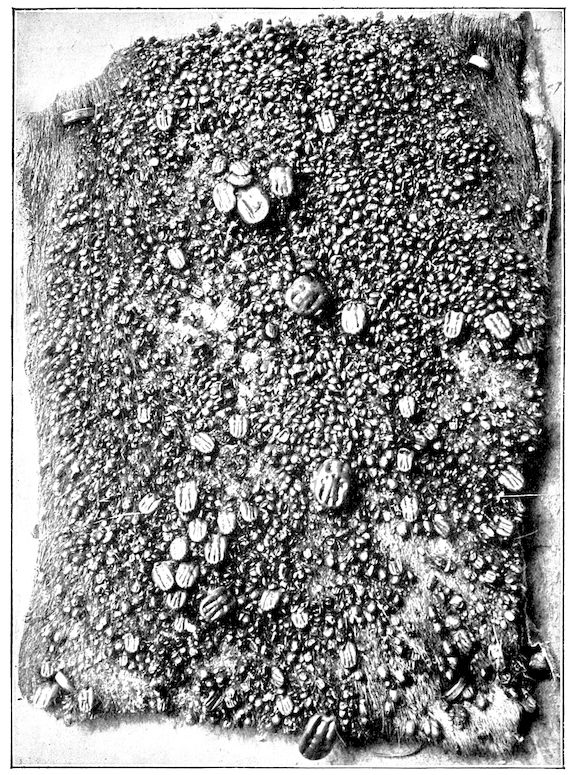

Fig. 8.—Transverse section through the middle region of the face in a pig suffering from osseous cachexia.

18In the final stages, the bones may be cut with a knife, and a time arrives when bony tissue seems completely to have disappeared; thus, as shown in Fig. 8 herewith, it was possible to cut the entire head of a pig into thin slices without the slightest difficulty. All parts of the head had been affected by the softening change.

From the chemical point of view, the diminution in mineral salts and in phosphate of calcium has long been recognised, but the degree of this change varies according to the phase. In human beings the proportions have been estimated as follows: Normal bone, 50 to 80 per cent. of phosphate of calcium; bone in persons suffering from osteomalacia, 5 to 20 per cent. of phosphate of calcium. The changes in the ossein have not been carefully studied. We only know that histologically the ossein becomes fibrillar, and that chemically it no longer retains its normal composition.